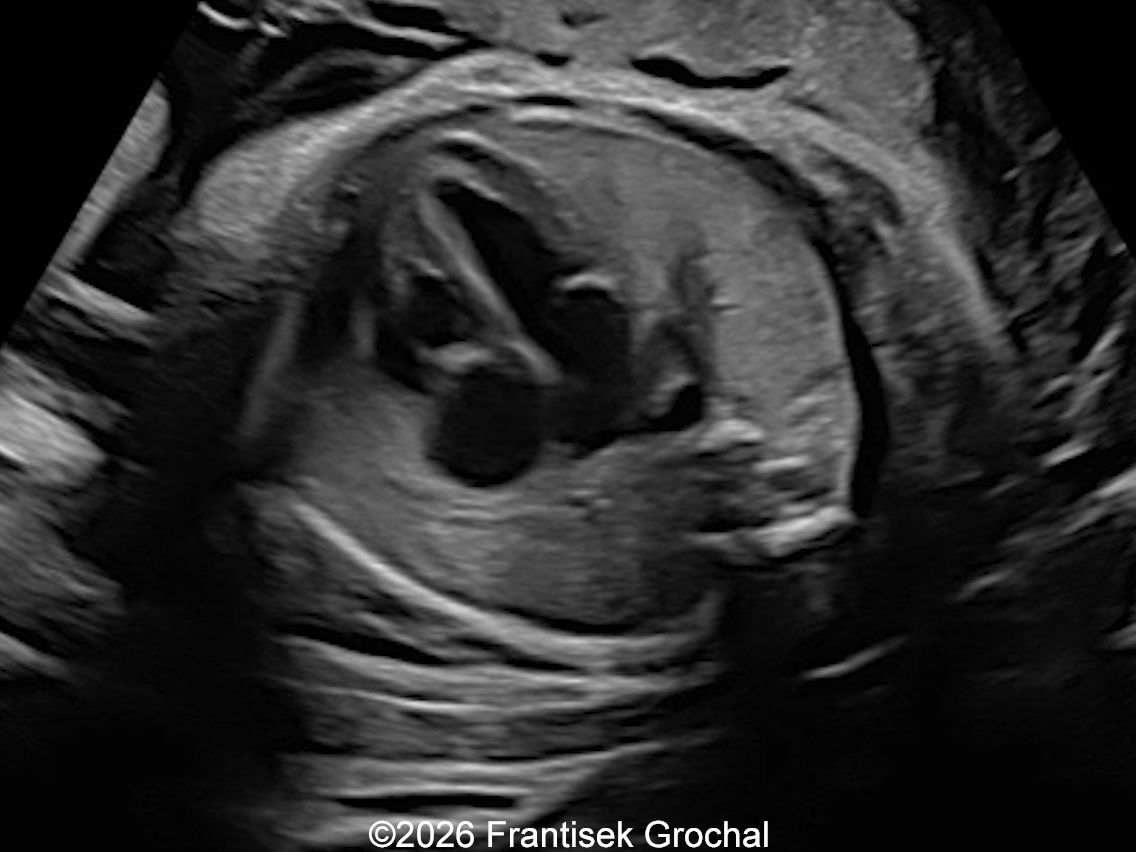

22+3 weeks of gestation – transverse thoracic view at the level of the four-chamber cardiac view demonstrating a well-circumscribed hyperechoic pulmonary sequestration. The heart is displaced to the right.

Image 2 22+3 weeks of gestation – transverse thoracic view at the level of the four-chamber cardiac view demonstrating a well-circumscribed hyperechoic pulmonary sequestration. The heart is displaced to the right.